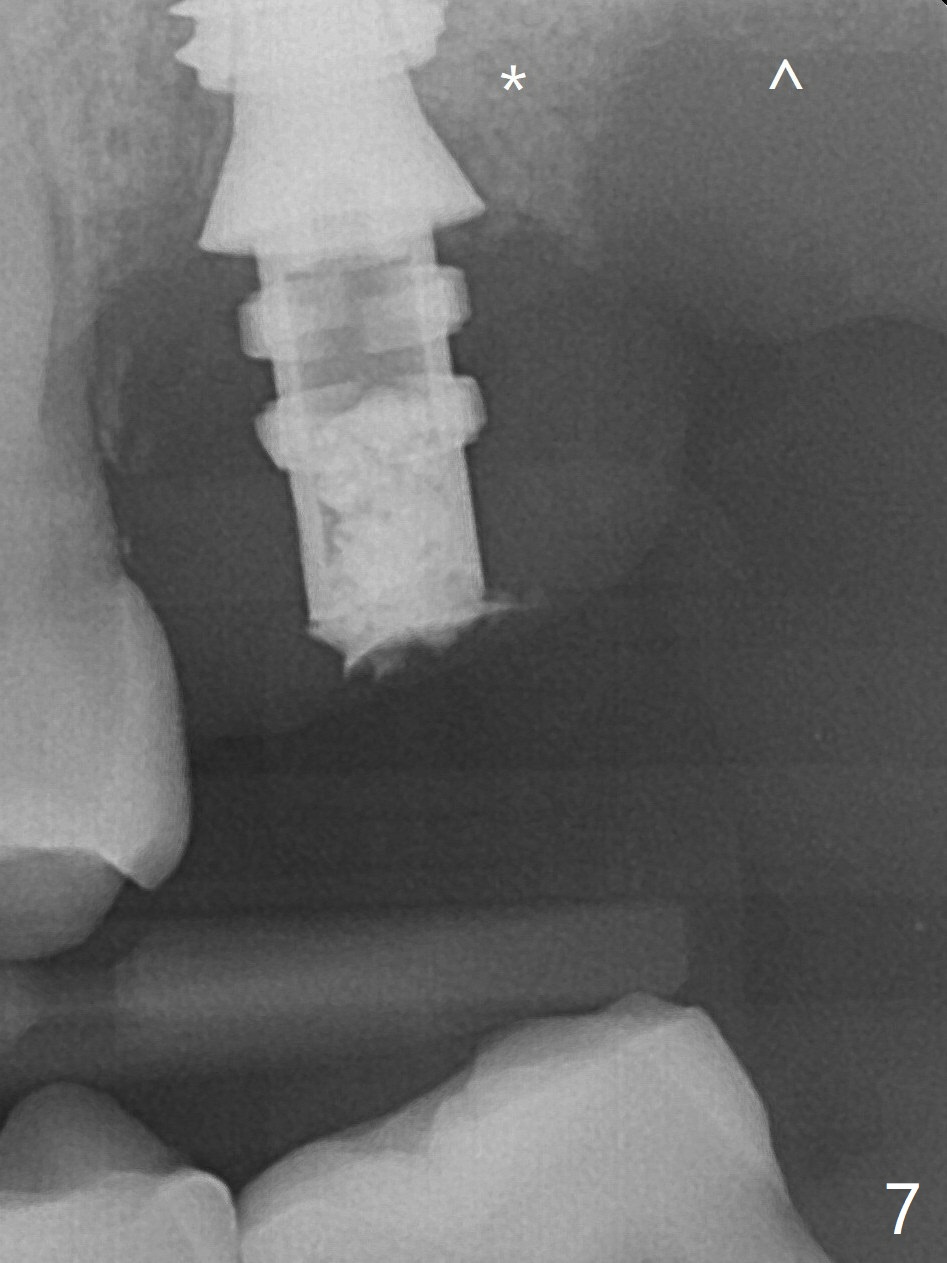

The temporary abutment holds an immediate provisional and Vanilla Graft/Osteogen (Fig.7 *) in place (^: distal crestal bone). Although the bone looks normal around the implant 7.5 months postop (Fig.4), the implant is unstable. The implant looks normal and is stable 13 months postop (Fig.10).